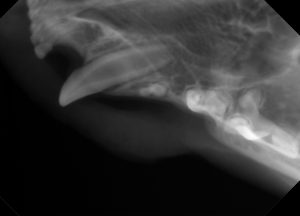

歯科レントゲン

麻酔中に行うことで、猫ちゃんに負担をかけることなく見た目ではわかりにくい歯の状態も確認できます。

★犬歯の後ろの歯が普通ではないのでレントゲンで確認します。

★どうやら乳歯?が抜けきらず、永久歯と並んで生えているようです。歯の距離が近すぎて乳歯を抜くと永久歯まで抜けてしまう可能性がある為、今回は無処置。歯磨き頑張ります。